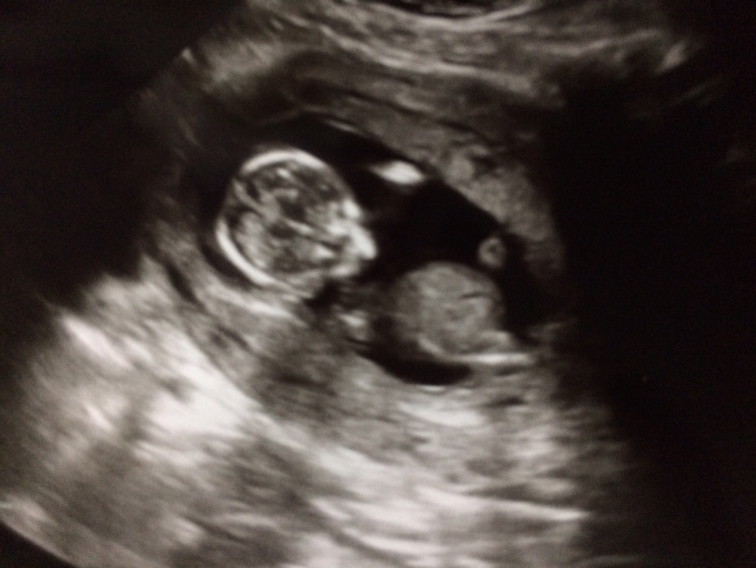

แม่ๆมีใครคลอด กพ 63 บ้างคะแม่บ้านนี้ 27 กพ 63 ตอนนี้ได้ 13 วีค 4 วัน ละ ตื่นเต้นสุดๆ อยากเจอหน้าสุด คุณหมอบอกว่า ผู้ชาย คะ